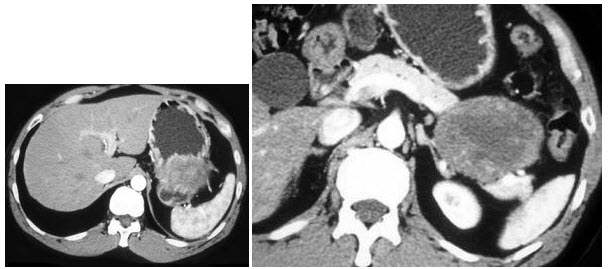

16、多项选择题

男,65岁,左腰部隐痛不适2月,CT平扫+增强如图所示,下列说法正确的是()

A.平扫时可见左肾局部隆起,腹主动脉旁、肾门部有等密度的块影

B.增强扫描可见左肾局部隆起病灶有不均匀强化

C.腹主动脉旁、肾门部的块影与左肾内的病灶强化方式相同

D.腹腔内未见积液,所示骨质亦未见破坏

E.考虑为左肾癌伴肾门淋巴结转移